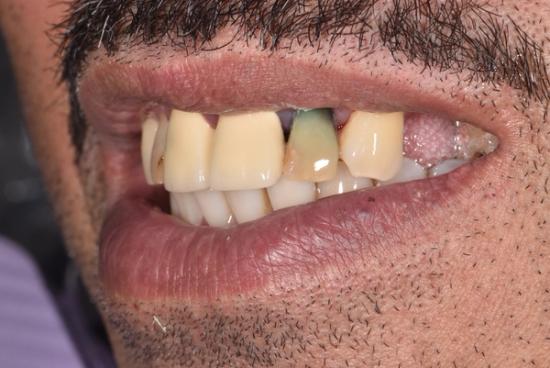

After Photo